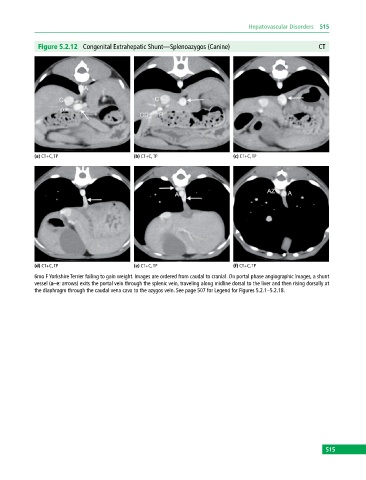

Figure 5.2.12 Congenital Extrahepatic Shunt—Splenoazygos (Canine) CT

(a) CT+C, TP (b) CT+C, TP (c) CT+C, TP

(d) CT+C, TP (e) CT+C, TP (f) CT+C, TP

6mo F Yorkshire Terrier failing to gain weight. Images are ordered from caudal to cranial. On portal phase angiographic images, a shunt

vessel (a–e: arrows) exits the portal vein through the splenic vein, traveling along midline dorsal to the liver and then rising dorsally at

the diaphragm through the caudal vena cava to the azygos vein. See page 507 for Legend for Figures 5.2.1–5.2.18.